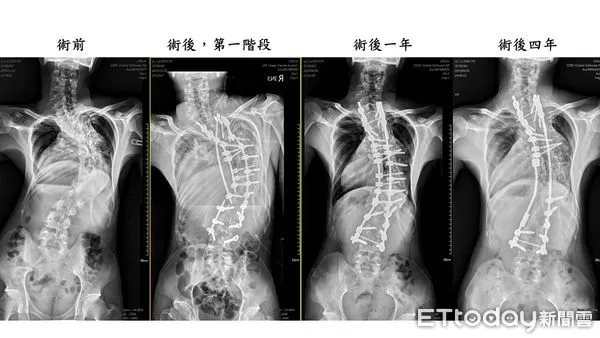

▲緬甸「龜背少年」番玉磊成功手術後每年定期追蹤,均維持良好狀態。(圖/記者蔡佩旻翻攝)

脊椎中心陳賢德陳賢德主任表示,「龜背少年」為駝背且脊椎嚴重側彎的病症,已壓迫到肺臟、心臟功能,影響生命安全。手術採用「3D導航輔助脊椎畸形截骨矯正手術」,單是第一次的手術就從早上7點到隔日凌晨3點,馬拉松式過程,終在團隊合作下順利完成手術。

▲緬甸「龜背少年」番玉磊成功手術後每年定期追蹤,均維持良好狀態。(圖/記者游瓊華翻攝)